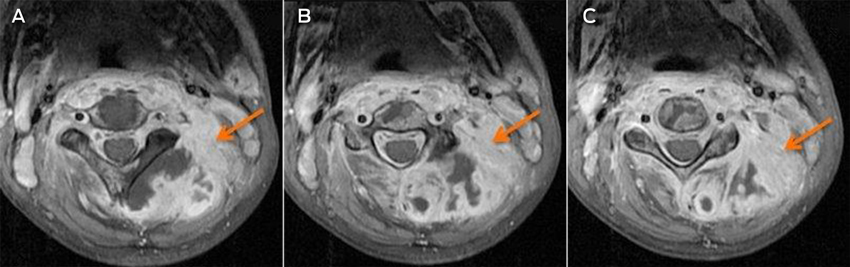

A magnetic resonance imaging scan on Day 7 identified an infiltrative lesion in the posterior paravertebral muscles, involving cervical vertebrae 1–5 and the spinal canal at that level (Box). The diagnostic possibilities were primary or secondary malignancy or infection. A pleural tap the next day drained 500 mL of blood-stained fluid. Laboratory results confirmed an empyema that grew S. aureus from the tap fluid.